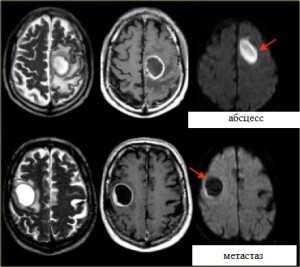

Диффузия:

Яркие очаги на диффузионное-взвешенных МРТ изображениях характерны для абсцессов, эпидермоидных кист, и острого инсульта. Опухоли имеют низкий сигнал на ДВИ МРТ головного мозга.

МРТ головного мозга. Аксиальные Т2-взвешенные МРТ, Т1-взвешенные МРТ с контрастировавшем и ДВИ МРТ.